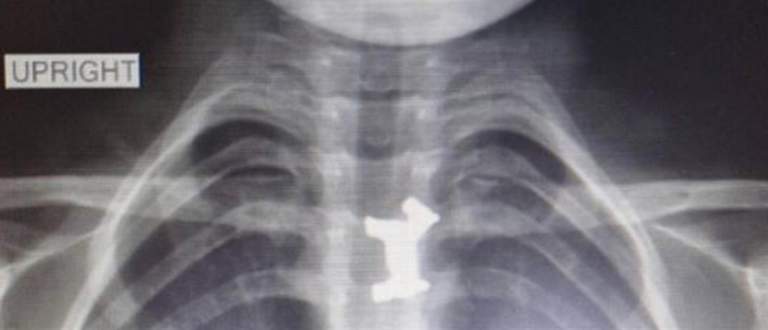

Σύμφωνα με πληροφορίες της voria, μετά από τις ακτινογραφίες διαπιστώθηκε πως το παιδί είχε καταπιεί ένα μεταλλικό σκυλάκι από επιτραπέζιο παιχνίδι που έπρεπε να αφαιρεθεί άμεσα, καθώς ήταν σε αρκετά δύσκολο σημείο.

Αφότου έγιναν όλες οι απαραίτητες εξετάσεις, αλλά και μετά από εκτίμηση παιδο-ΩΡΛ, υπεβλήθη σε οισοφαγοσκόπηση υπό γενική αναισθησία για την αφαίρεσή του από τον οισοφάγο.